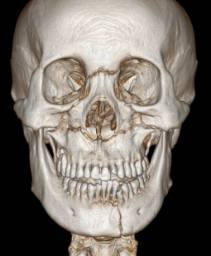

取模型:医生先在口中取阴模,然后用石膏灌注模型,还原牙列形态。石膏模型可以使医生直观地观察牙齿排列状况,从而制定矫治方案。同时,石膏模型也是进行治疗前后对比的重要依据。最新科技可以让我们采用口内扫描仪代替常规取模,或者在取模后通过模型扫描,获得数字化模型。

石膏模型(上)与数字化模型(下)